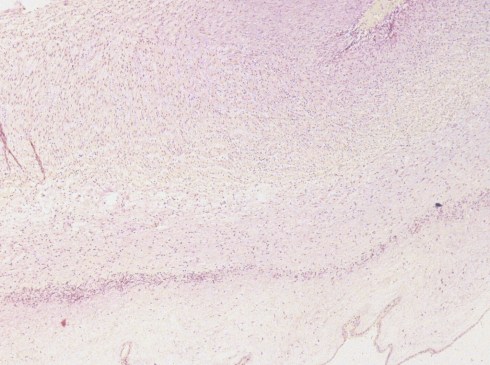

The variation in pattern is some cases could be the result of the response elicited by the organism. For example, syphilis might initiate a chronic response, which would not only favor chronic inflammatory cell migration, but also modify the types of chemical mediators, which could alter the pathology, perhaps favoring vascular necrosis. Silver stains frequently demonstrate great numbers of spirochetes in Wharton’s jelly that might stop many inflammatory cells from extending far from the umbilical vessel (Fig 11) (9).

Fig 11a) SNF lesion in a stillborn infant with syphilis.

Fig 11b) Higher power demonstrating chronic inflammation in the umbilical vein media.

Fig 11c) Silver stain demonstrating a spirochete (arrow). They were through out Wharton’s Jelly.